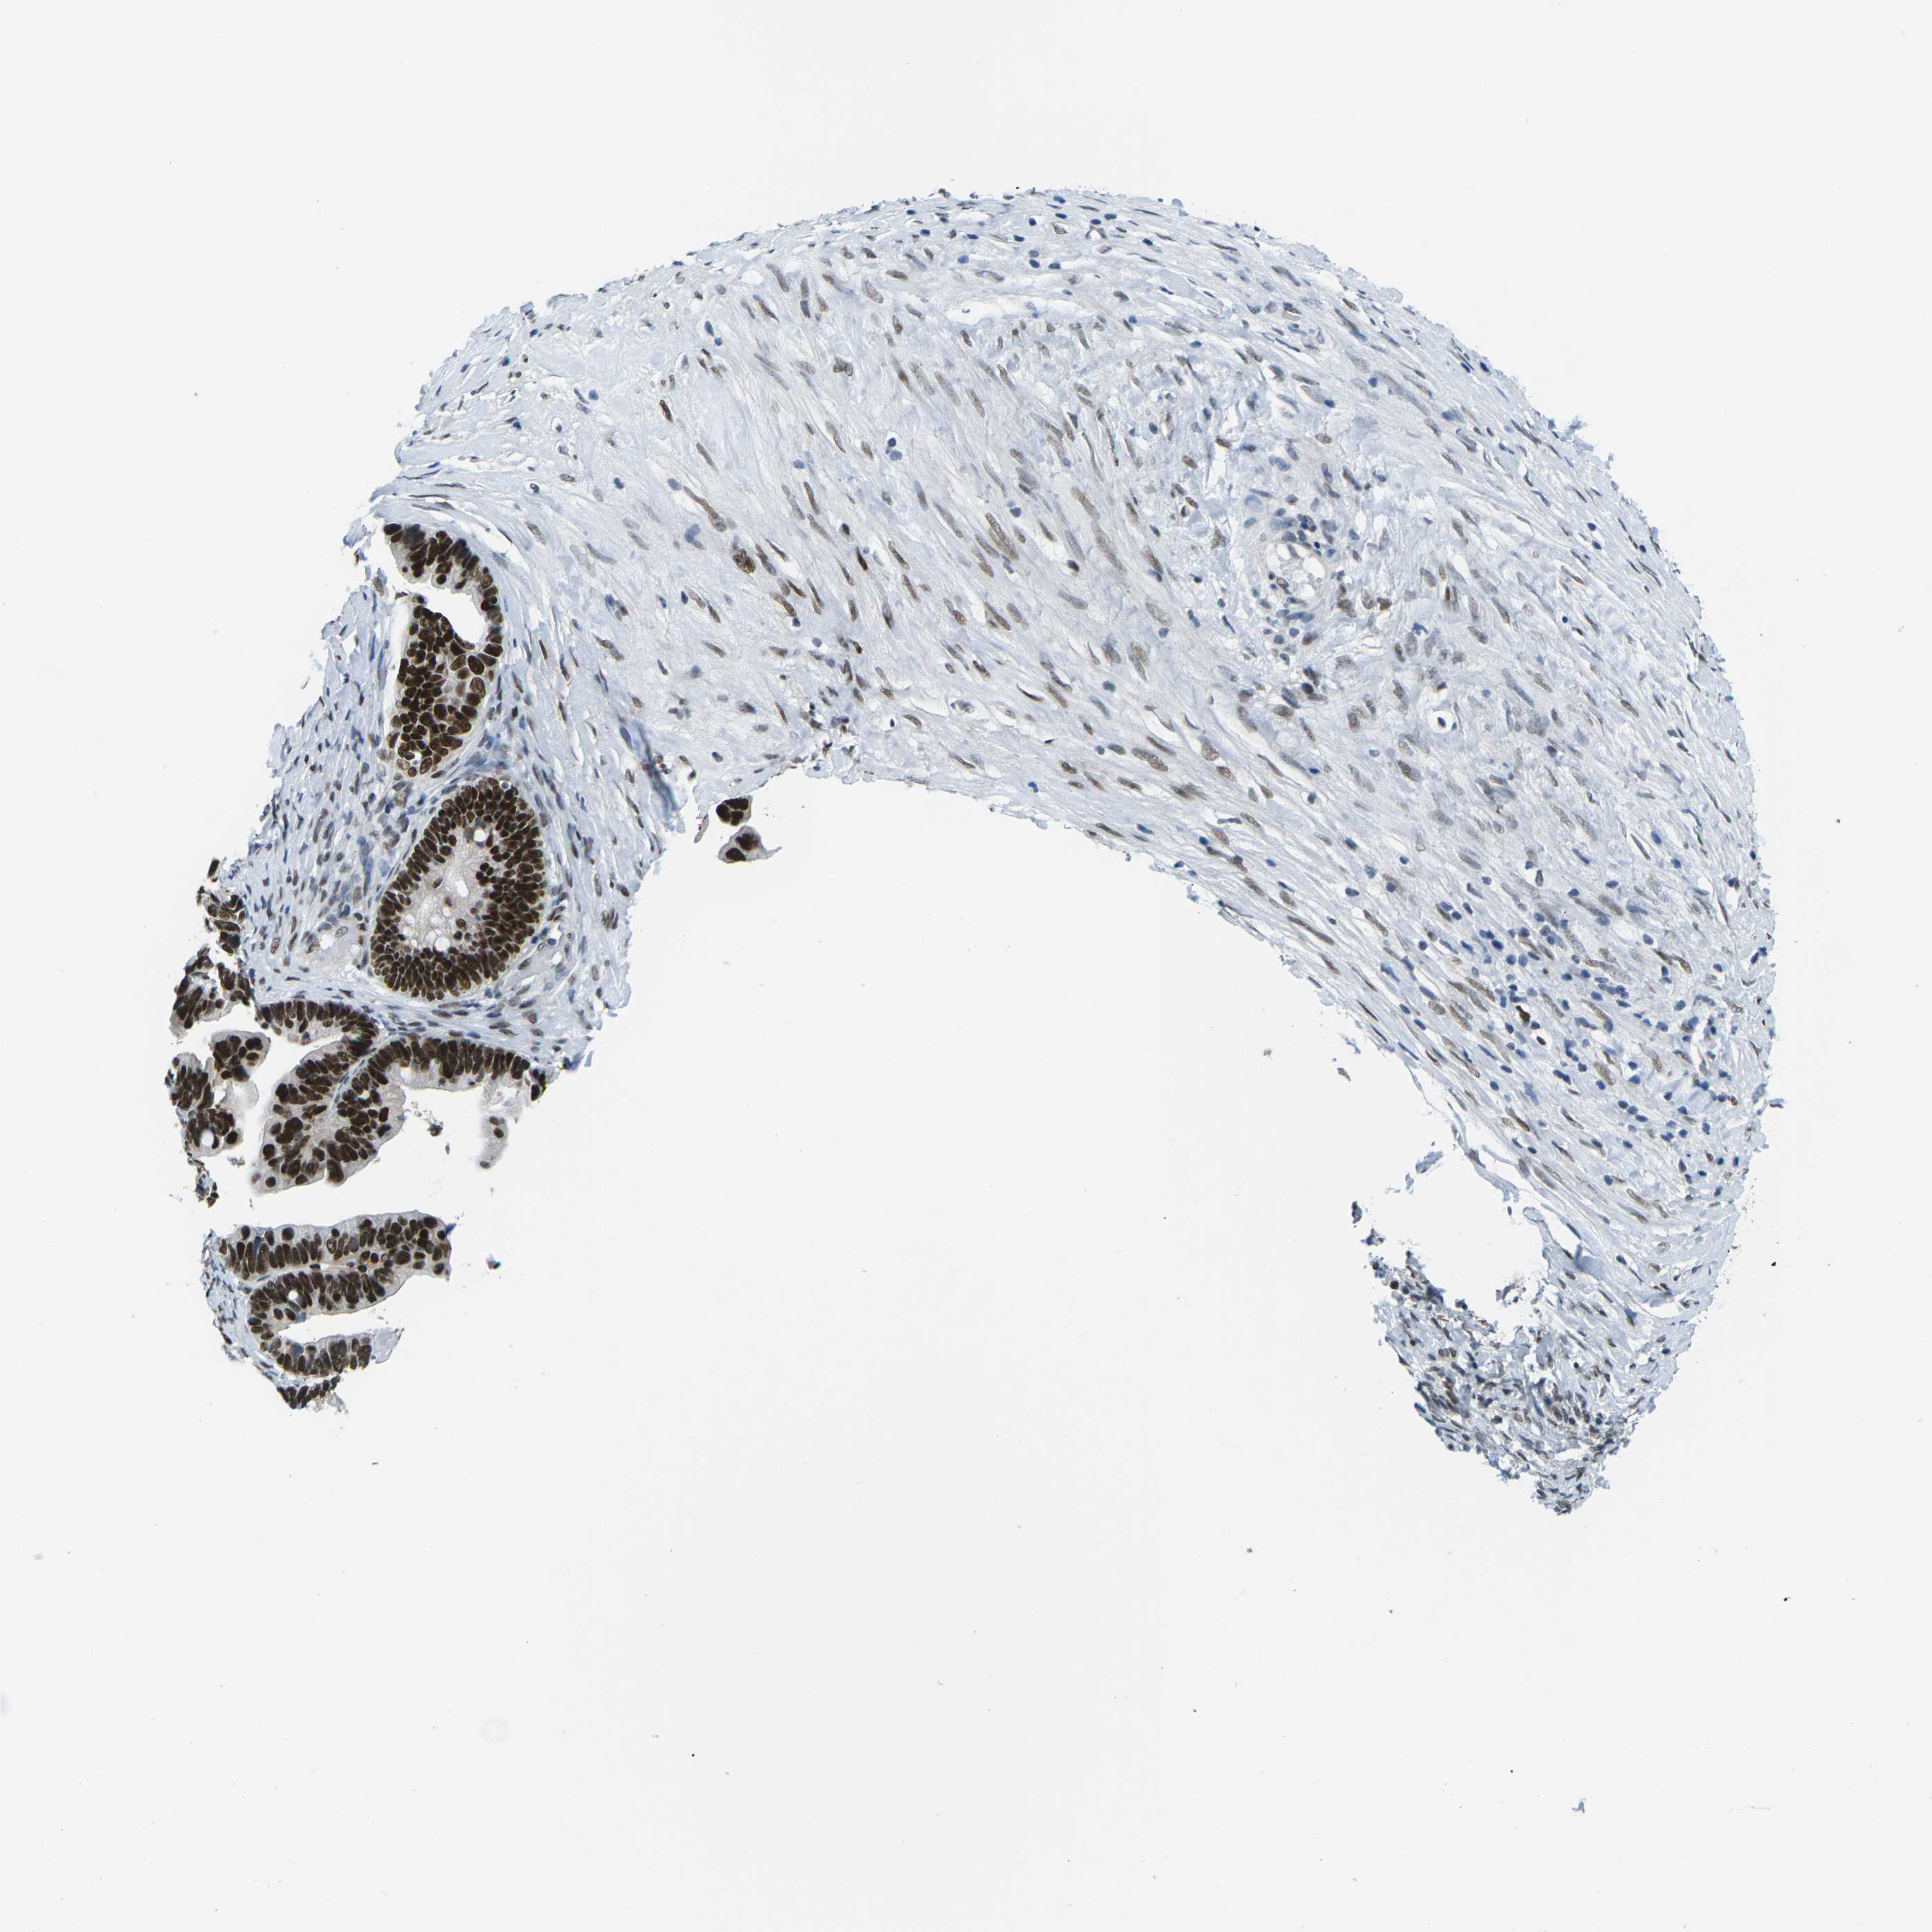

OVARIAN CANCER - Protein expressioni

A mouse-over function shows sample information and annotation data. Click on an image to view it in a full screen mode. Samples can be filtered based on level of antibody staining by selecting one or several of the following categories: high, medium, low and not detected. The assay and annotation is described here.

Note that samples used for immunohistochemistry by the Human Protein Atlas do not correspond to samples in the TCGA dataset.

Antibody stainingi

Antibody staining in the annotated cell types in the current human tissue is reported as not detected, low, medium, or high, based on conventional immunohistochemistry profiling in selected tissues. This score is based on the combination of the staining intensity and fraction of stained cells.

Each image is clickable and will lead to virtual microscopy that enables deeper exploration of all samples and also displays staining intensity scores, fraction scores and subcellular localization as well as patient and tissue information for each sample.

Antibody HPA012510

Antibody CAB008388

Cystadenocarcinoma, serous, NOS

Carcinoma, endometroid

Cystadenocarcinoma, mucinous, NOS

Carcinoma, NOS